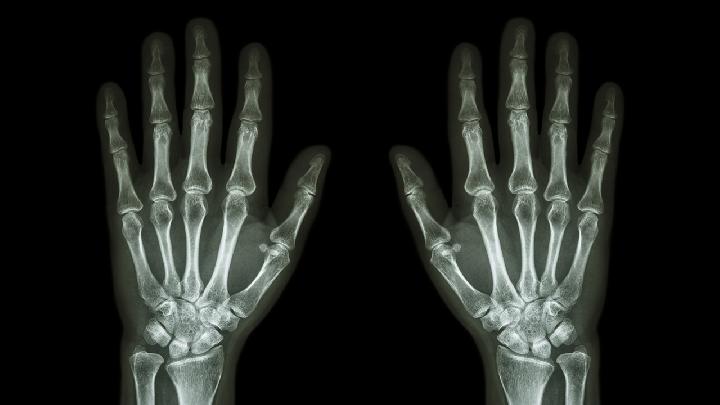

骨肿瘤是发生于骨骼或其附属组织的肿瘤。有良性,恶性之分。恶性骨肿瘤,就是老百姓常说的“骨癌”,其发展迅速,预后不佳,死亡率高。恶性骨肿瘤分为原发性和继发性。从体内其他组织或器官的恶性肿瘤经血液循环、那么骨癌有哪些危害表现呢?

骨癌是一种恶性的肿瘤疾病,骨癌有很多种比较常见的类型,比如说骨肉瘤类型,软骨肉瘤型以及纤维肉瘤型。这种病发病后最容易连累到人的骨骼,但不全是连累到骨骼,身体其他组织也会受到连累。当发生过之后可以影响到人的造血系统,使人发生贫血病。此病发病之后会使得患者关节疼痛或者是关节肿胀,身体远端的肢体可能会有麻木的感觉,还有可能压迫到人的神经以及血管,影响到患者的关节活动能力,影响到全身的血液循环。